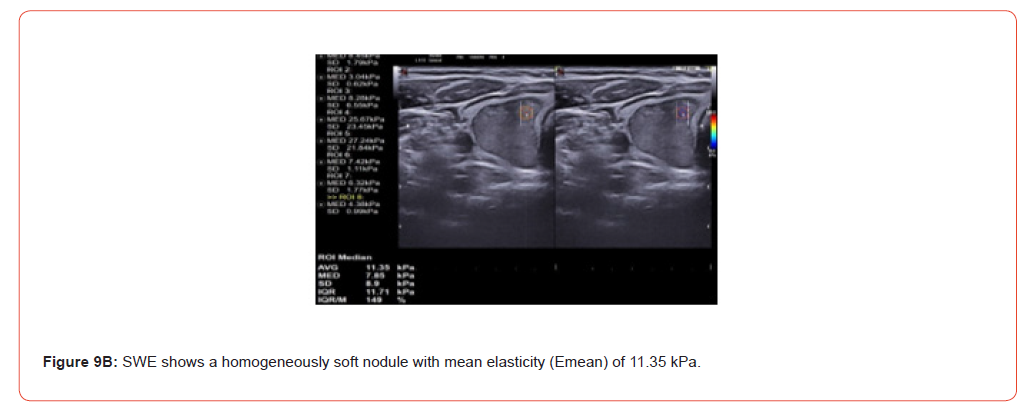

Figure 9 and 10 show representative case of benign and malignant thyroid nodule.